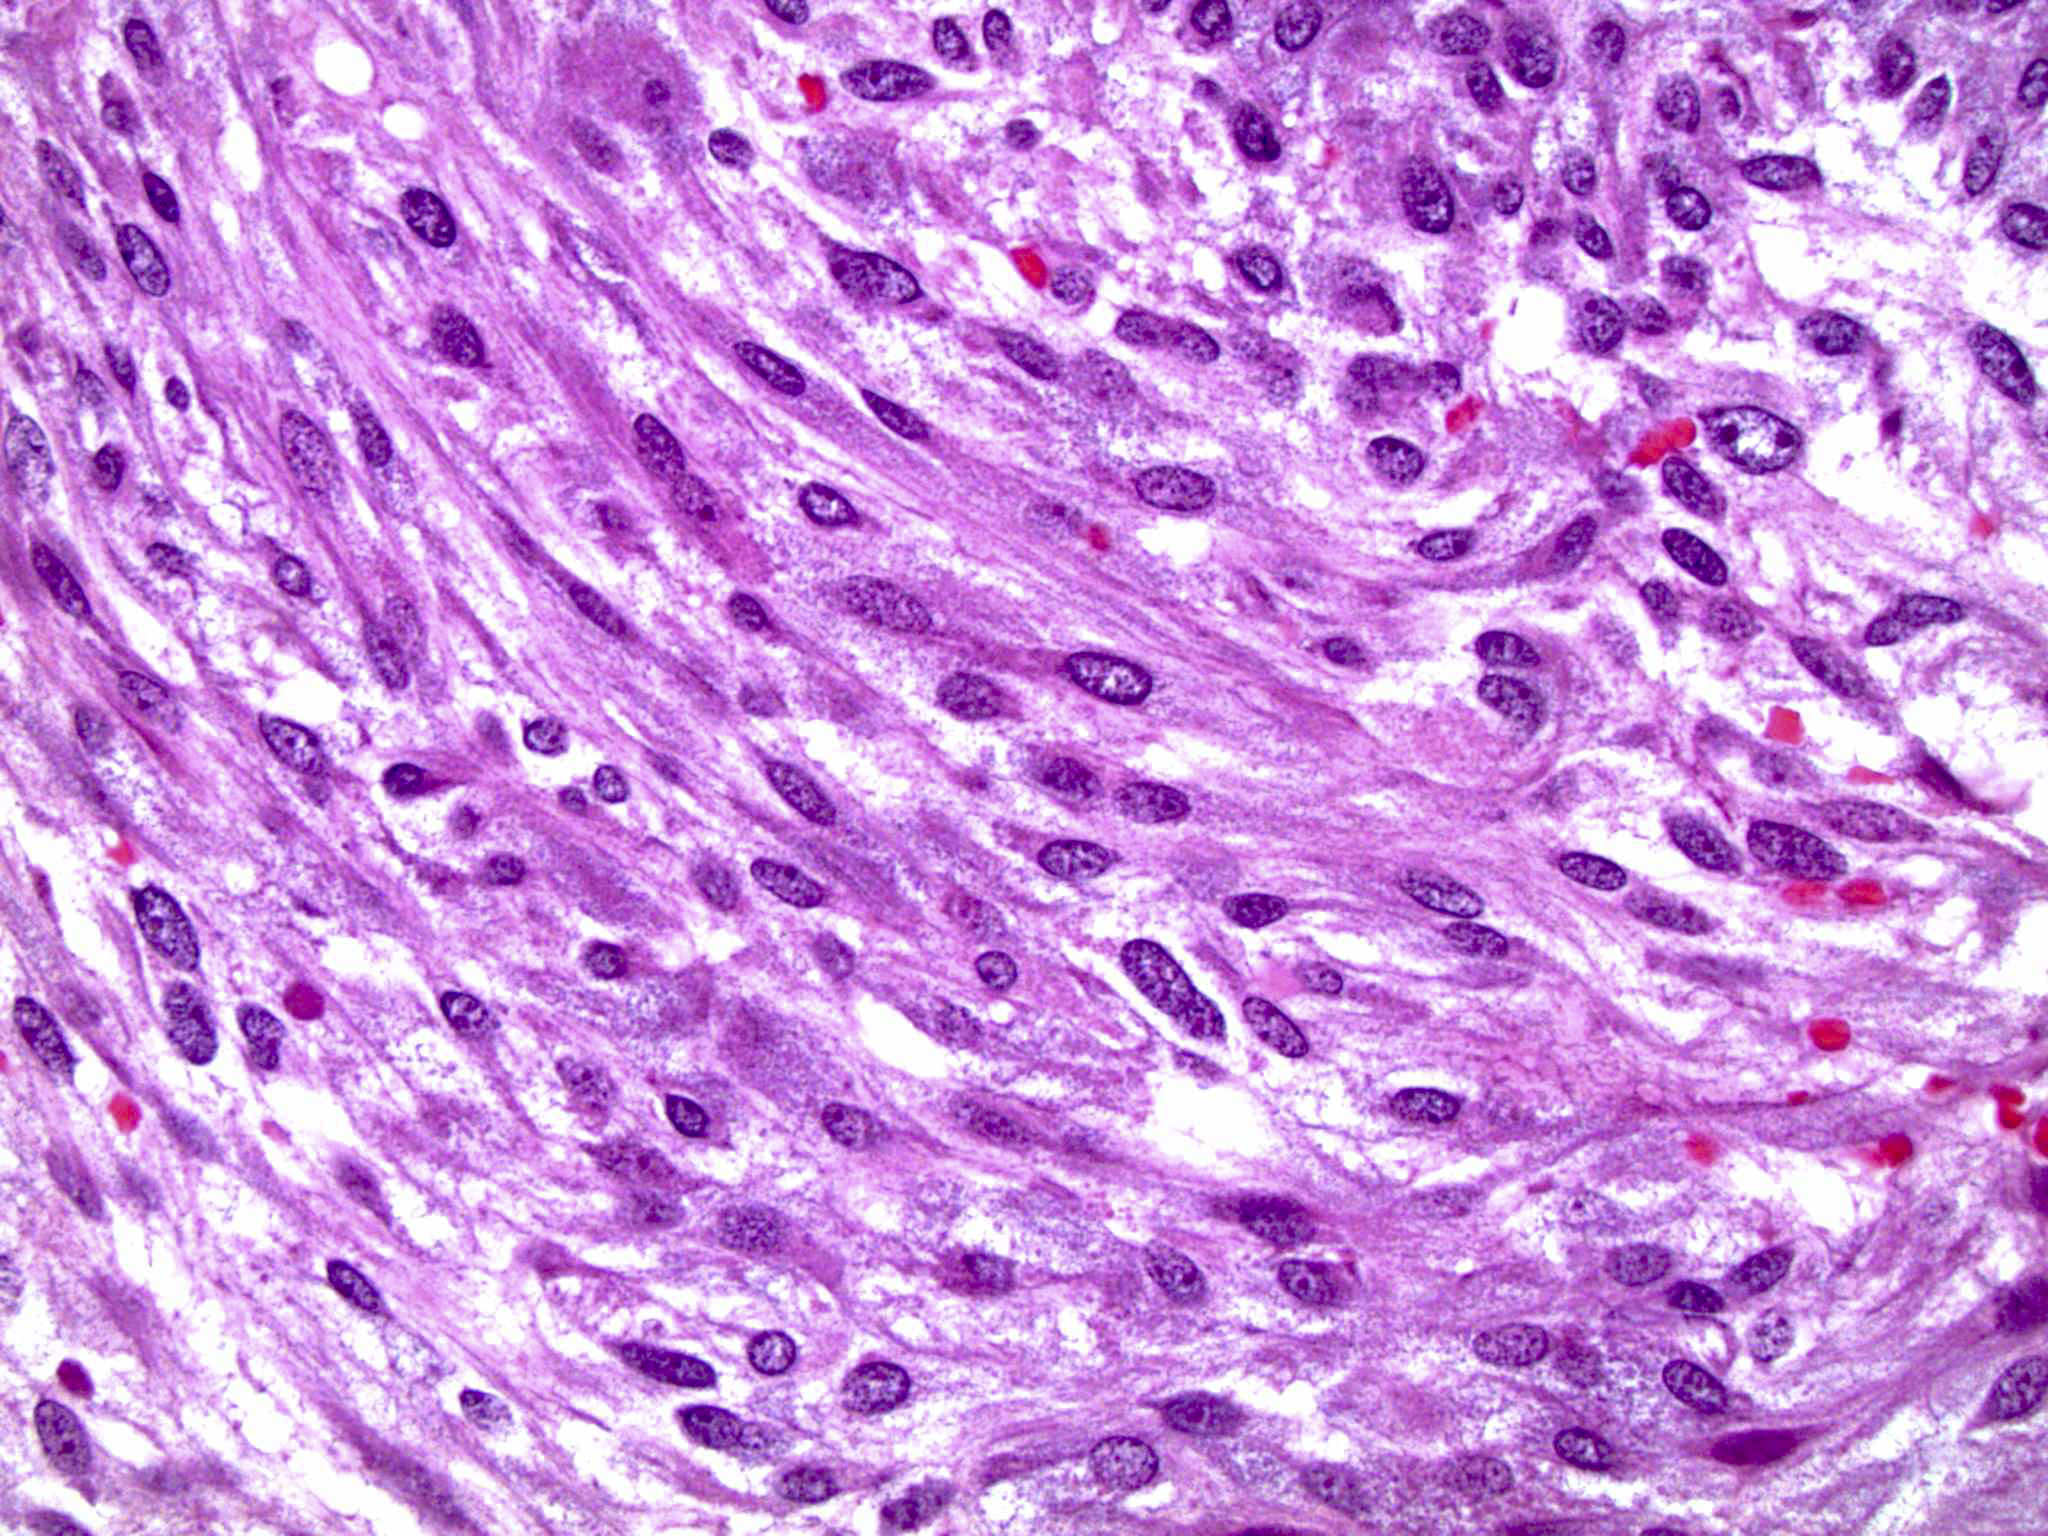

Microscopic (histologic) description

- Typical morphology: epithelioid cells with abundant, eosinophilic / amphophilic, granular cytoplasm and round / ovoid, vesicular / salt and pepper nuclei, arranged in a nested / zellballen pattern and separated by fibrovascular septae with sustentacular cells (Am J Surg Pathol 2004;28:94, World J Clin Cases 2014;2:591, Endocr Pathol 2022;33:90)

- May have focal pleomorphism, nuclear hyperchromasia, low mitotic activity or clear cytoplasm

Microscopic (histologic) images

Contributed by Theodorus H. van der Kwast, M.D., Ph.D., Michelle R. Downes, M.D., Debra L. Zynger, M.D. and David Cohen, M.B.B.Ch., M.D.

- Sustentacular cells: S100, SOX10

- Microscopic description: This specimen shows an unencapsulated, monomorphous population of round tumor cells in a nested / zellballen pattern with delicate vascular septa and intervening extravasated red blood cells. It predominantly involves the lamina propria of the bladder but in 1 tissue piece clearly involves muscularis propria. The tumor cells have abundant amphophilic cytoplasm and vesicular chromatin with occasional small nucleoli. There is no necrosis, diffuse growth pattern or vascular space invasion identified. The mitotic count is (maximally) 1/10 high power fields. Immunohistochemistry shows the tumor cells to be positive for GATA3 with strong and diffuse expression of synaptophysin and chromogranin, as well as retention of SDHB staining. The tumor cells are negative for AE1 / AE3, HMWK and p63. The Ki67 proliferation index is < 1%. S100 shows faint nuclear and cytoplasmic staining with occasional sustentacular cells identified.

- Microscopic description: Sections show unremarkable surface urothelium with a lesion in the deep lamina propria comprised of large eosinophilic cells with hyperchromatic, focally enlarged nuclei with occasional intranuclear inclusions. A fine vascular plexus is identified in some areas. Necrosis and hemorrhage are not identified. Mitotic rate = 1/10 high power fields (field of view [FOV] = 0.55 mm). The lesion extends to the cauterized base of the specimen. Immunostains confirm the lesion expresses synaptophysin, chromogranin and GATA3. SDHB is retained. AE1 / AE3, CD45, p63 and NKX3.1 are negative.